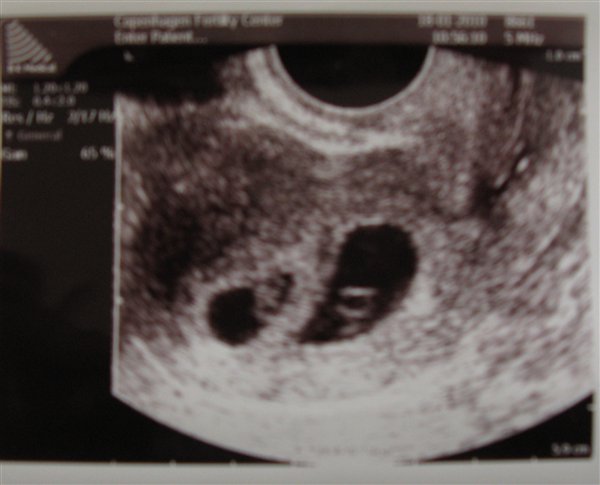

Det bliver endelig min tur, og med rystende ben bliver jeg arrangeret i bøjlerne. Han finder med det samme livmoderen og jeg får øje på to mørke klatter. Jeg udbryder et gisp, men husker mig selv på, at blommesækken kan ligne en ekstra graviditet.

Lægen spørger om jeg er okay. Min mor svarer for mig, at jeg er nervøs for om der er liv. Lægen siger så, at jeg skam er MEGET gravid. Han kigger på mig og siger så: Du skal have TVILLINGER.

Jeg begynder at hulke på livet løs, og han må bede mig ligge stille, så jeg kan se hjerteblink. Begge tvillinger er store, flotte og blinker derudaf.

Her et billede af Pomfrit I og Pomfrit II